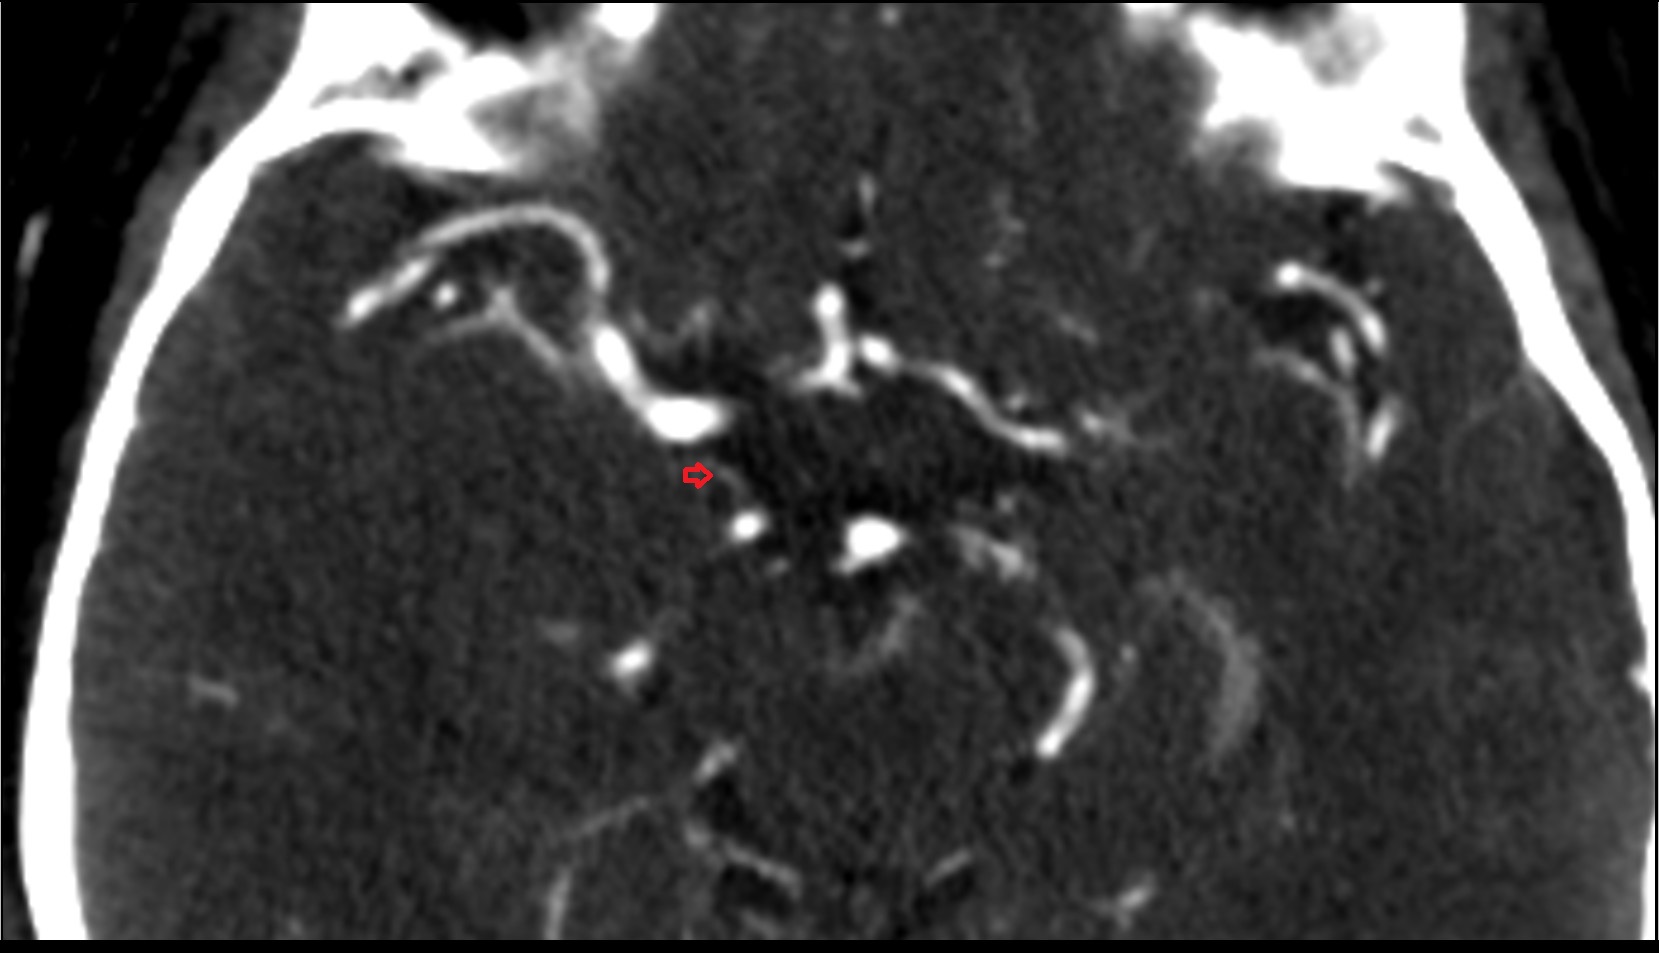

- Posterior cerebral artery (P1 Segment)

- Posterior cerebral artery (P2 Segment)